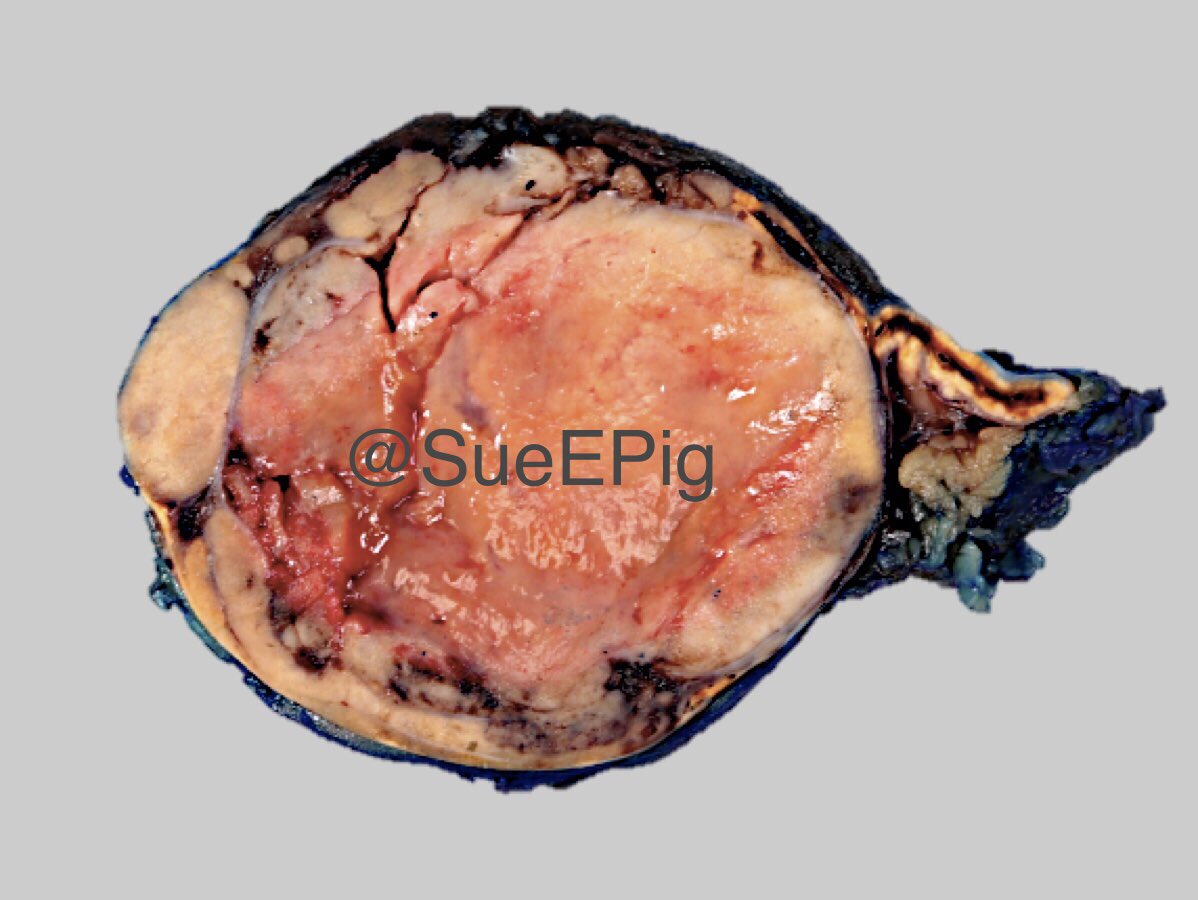

Gross description

- Weight usually < 50 grams (in pediatric patients may weight up to 500 grams) (Mod Pathol 2011;24:S58)

- Size usually < 5 cm

- Unilateral, solitary, golden yellow

- May have focal dark areas corresponding with hemorrhage, lipid depletion, increased lipofuscin

- Functional adenoma may result in atrophy of ipsilateral or contralateral adrenal cortex

Gross images